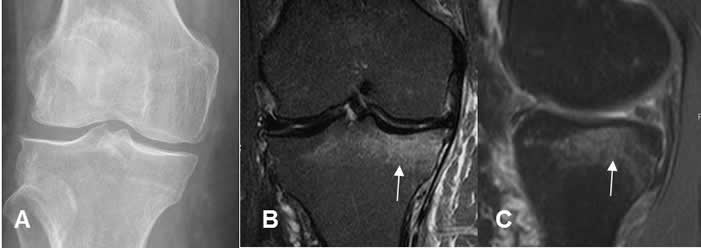

Fig 25. Fractura de la cabeza femoral.

A: Rx AP. Línea radiolúcida en la cabeza femoral, sugestiva de fractura.

B: RM coronal en T1 y C: RM coronal en STIR. Edema óseo en la cabeza femoral, con imagen hipointensa y en sentido oblicuo, que corresponde a fractura.